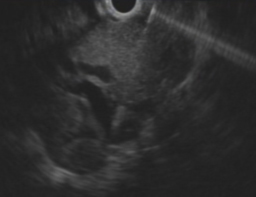

実際の症例をお示します。患者さんは膵癌により胆管が詰って黄疸が出現しました。膵癌が十二指腸へ広がり内腔が狭くなったため、内視鏡が通過せず、通常のERCPによるステント留置が不可能でした。そのためEUS-BDを施行しました。胃内から超音波内視鏡で肝臓の中の胆管を観察して、胆管を穿刺します(図1)。胆管に造影剤を満たし(図2)、ガイドワイヤーを挿入し、胆管金属ステントを留置しました(図3,4)。この手技により、体内にチューブを埋め込む形で胆汁の流れを確保することができ、黄疸は改善しました。

図1図1